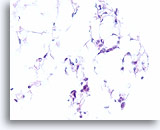

Lobulair carcinoom, Borst FNA, Celblok.

In dit veld worden enkele losgekomen lobulaire carcinoomcellen weergegeven die vermengd zijn met het vetweefsel. Twee andere cellen zijn verdacht voor invasiviteit in het weefsel (pijl).

40X

Lobulair carcinoom, Borst FNA, Celblok.

In dit veld worden enkele losgekomen lobulaire carcinoomcellen weergegeven die vermengd zijn met het vetweefsel. Twee andere cellen zijn verdacht voor invasiviteit in het weefsel (pijl).

40X